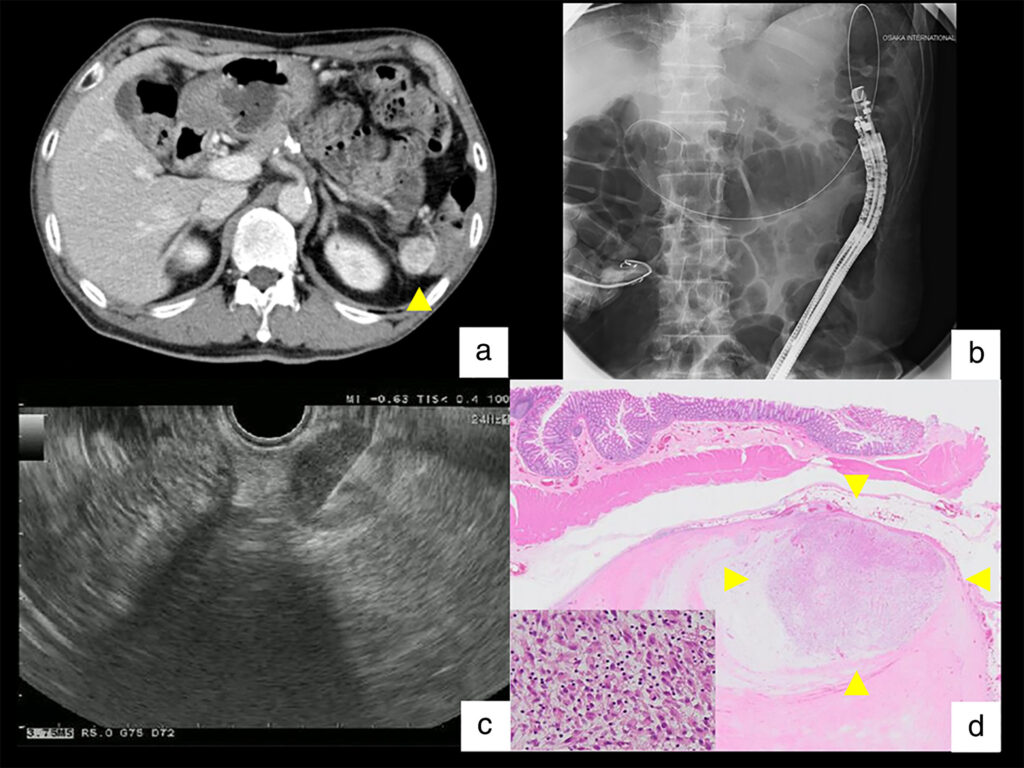

- Physical exam and MRI/CT scan

- Core needle biopsy with histologic grading

- Pathology: pleomorphic spindle cells, no distinct line of differentiation